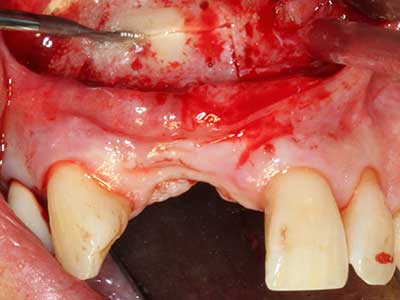

Aplicación: Partición ósea / Cortical Split

El tejido óseo no solo tiene un contenido puramente mineral, sino que también presenta una importante proporción de fibras de colágeno. Esto no solo garantiza una buena resistencia a la presión, sino también una cierta flexibilidad, que puede aprovecharse para la realización de aumentos. En la plastia de expansión clásica a efectos de una partición ósea, la cresta maxilar atrofiada se divide en su eje longitudinal y, tras alcanzar una profundidad de osteotomía suficiente, se extiende con cuidado (fig. 13-16), en un caso ideal sin desperiostizar de forma visible el maxilar (Brugnami, Caiazzo et al. 2014, Stricker, Fleiner et al. 2014). Los sistemas de tornillos y placas con distancia de expansión creciente han demostrado su eficacia para distanciar entre sí las dos tablas óseas por debajo del umbral de rotura. Por regla general, se requieren anchuras de hueso residual de al menos 3 a 4 mm (Chiapasco, Zaniboni et al. 2006) para garantizar una flexibilidad y una cobertura ósea suficientes de los implantes que van a incorporarse. En caso necesario, una osteotomía de descarga vertical unilateral o bilateral puede mejorar la flexibilidad. Como alternativa a la técnica clásica se ha descrito una combinación con otras técnicas de aumento, sobre todo en la parte bucal.

Con el uso de sierras piezoeléctricas la división se efectúa de forma especialmente cuidadosa y sin pérdidas importantes de las dimensiones, por lo que no se han encontrado diferencias significativas entre los implantes realizados en el maxilar dividido y en la cresta alveolar no deficitaria (Chiapasco, Zaniboni et al. 2006, Danza, Guidi et al. 2009). No obstante, precisamente en la partición profunda y limitada de forma local, es preciso asegurarse de que exista una adecuada irrigación por agua para evitar que se produzcan sobrecargas térmicas en las áreas de osteotomía apical.